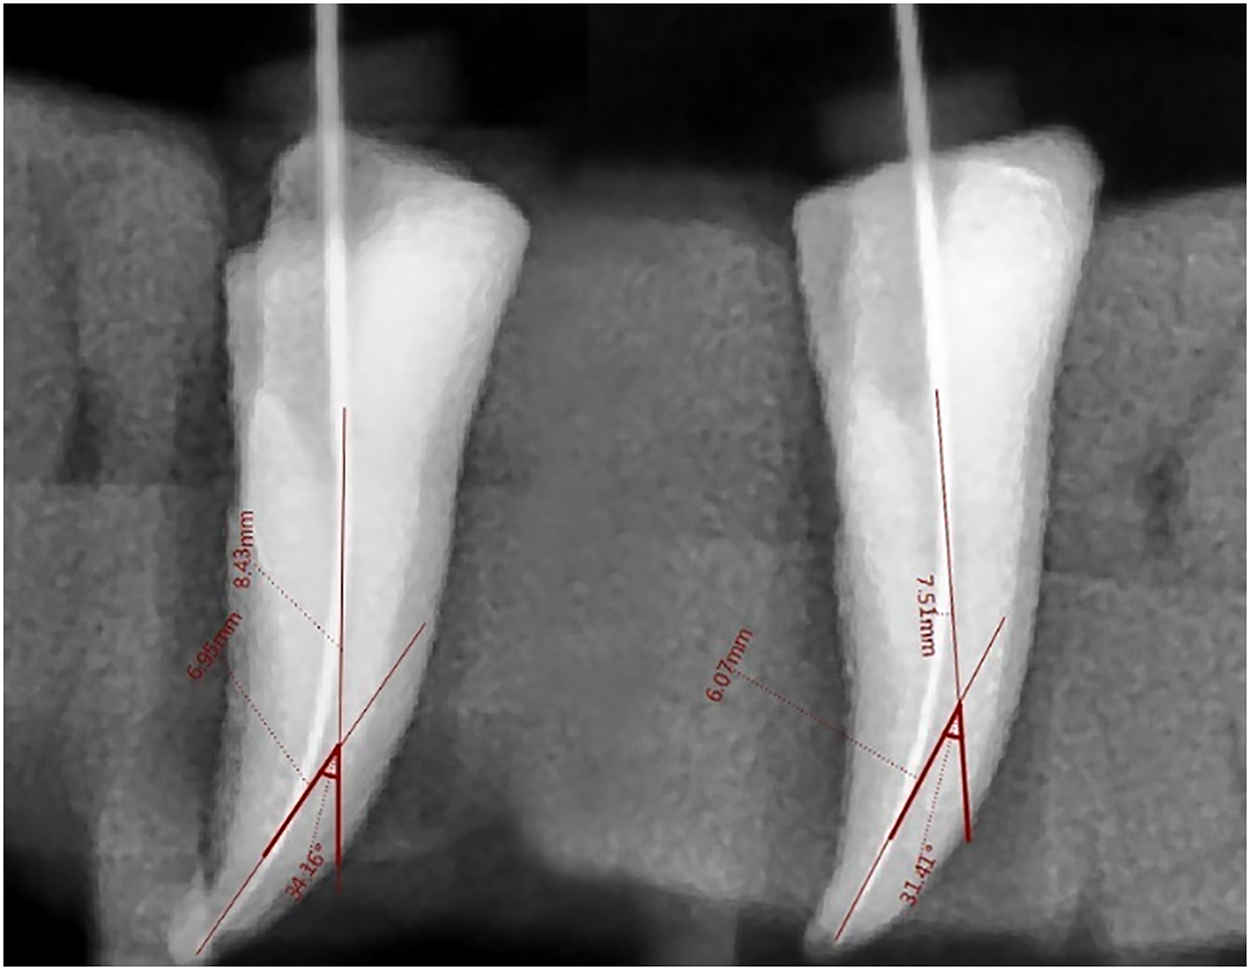

Lastly, sterile paper tips were used to dry the canals. Only the researcher prepared each channel. The following instrumentation, the same circumstances as for initials were used for the specimens to take radiographs using digital dental periapical imaging (Figs. 1–3). The identical method as previously described was used to take the post-operative photos. The same procedure was used to measure the specimens’ canal curvatures. The initial measurement was of the post-instrument canal curvature.

Fig. 1. Pre- and post-instrument curvature change in group A.